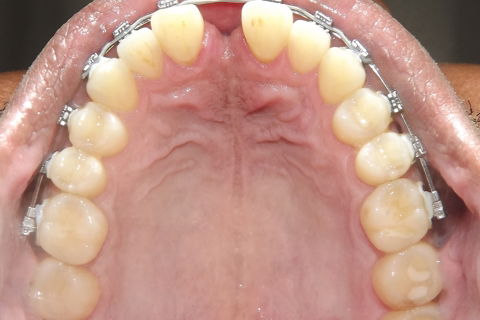

fotos finais, paciente encaminhado para implantes.

Paciente do sexo masculino, 36 anos, brauifacial. Relatava que os Diastemas lhe incomodavam muito, e em tratamento anterior o profissional fez exo de 2 incisivos centrais inferiores e instalou Prótese movel com 4 incisivos, após um tempo de uso a prótese começou a incomodar. em planejamento com o implantodontista ficou definido o fechamento dos diastemas e reabilitação dos elementos 41 e 31 com implantes.